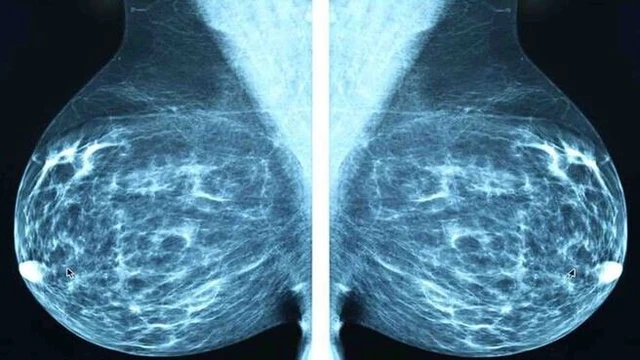

Ung thư vú giai đoạn đầu được xếp vào giai đoạn sớm có tiên lượng tốt và có tỷ lệ chữa khỏi cao. Vì vậy, việc nhận biết hình ảnh ung thư vú giai đoạn đầu sẽ giúp phát hiện sớm và tăng cơ hội điều trị cho người bệnh.

Ung thư vú là một trong những căn bệnh gây tử vong cao nhất ở nữ giới. Vì vậy, việc nhận biết các triệu chứng của bệnh, nhận dạng được hình ảnh ung thư vú là vô cùng quan trọng. Hãy trang bị đầy đủ kiến thức về căn bệnh này để bảo vệ sức khỏe của bạn.

Ung thư vú là một trong những loại ung thư thường gặp và nguy hiểm ở phụ nữ trên khắp thế giới. Việc nhận biết các triệu chứng ung thư vú sớm có thể giúp phát hiện và điều trị bệnh kịp thời.